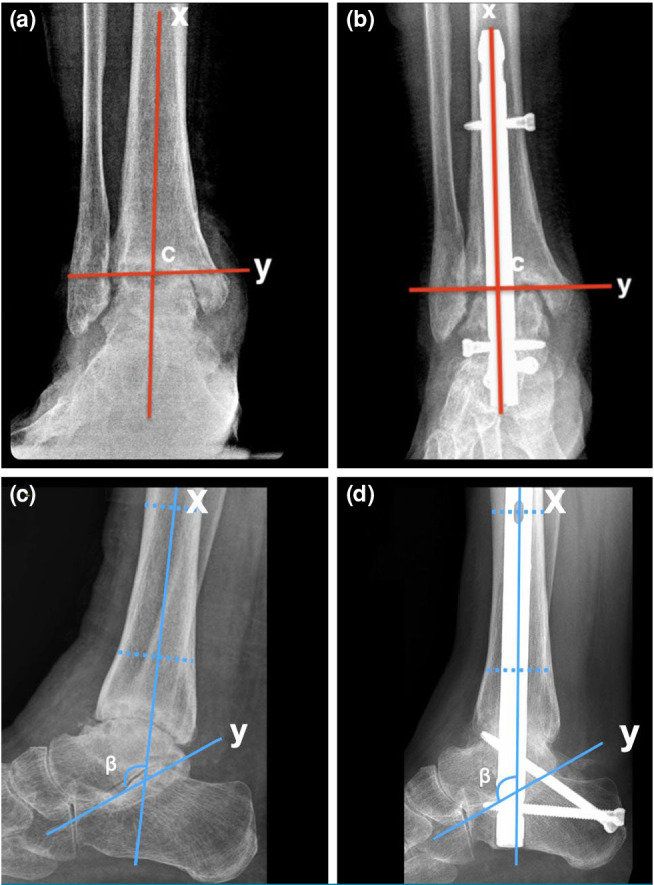

Patients and methods: Between January 2011 and December 2022, a total of 62 patients (21 males, 41 females; mean age 53.81±16.68 years; range 18 to 82 years) who underwent TTCA with retrograde intramedullary nail were retrospectively analyzed. The patients were classified as open (n=30) or arthroscopy (n=32) based on the method used for joint debridement. Data including demographic characteristics, pre-and postoperative radiographs, skin-to-skin operative times, and fluoroscopy times were recorded. Tibiotalar and subtalar union rates, coronal and sagittal ankle alignment examined through coronal tibiotalar (CTT) and sagittal tibiotalar (STT) angles were also noted. Functional outcomes were measured using the American Orthopaedic Foot and Ankle Society Ankle-Hindfoot Score (AOFAS-AHS) and Visual Analog Scale (VAS). Complications were evaluated.

Results: A total of 34 ankles (n=30) underwent open TTCA, while 34 ankles (n=32) had arthroscopic TTCA. Baseline characteristics and follow-up duration were similar between the groups (p>0.05). The overall fusion rate (tibiotalar and subtalar) was 94.1% in the open group and 85.3% in the arthroscopic group (p=0.425). Both open and arthroscopy groups achieved satisfactory coronal and sagittal ankle alignment. The median CTT angles were 94° and 91°, and STT angles were 109° and 112°, respectively. The arthroscopy group had significantly shorter operative time, fluoroscopy time, and hospital stay (p<0.001, p=0.019, p<0.001, respectively). No significant differences were found in complication rates, postoperative AOFAS-AHS, and VAS scores (p>0.05).